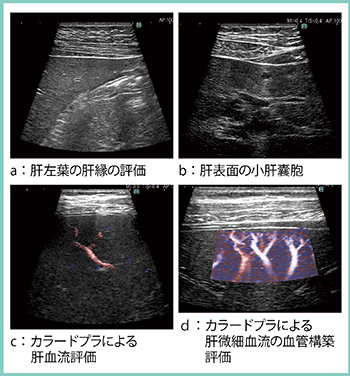

さらに,同社が2009年に世界で初めて実現した,半導体技術による乳腺用リニアプローブ「CMUT」を進化させた「4G CMUT」が登場した。従来よりも広帯域化・高感度化を実現しており,表在臓器をはじめ,深部臓器・血管など,このプローブ1本で全身の超音波検査をカバーできるようになった。実際の画像(図2)を見ると,肝左葉の肝縁の評価(a)や肝表面の小肝囊胞(b)の描出,カラードプラによる肝血流評価(c)および肝微細血流の血管構築評価(d)も可能である。

図2 次世代型高周波プローブ(4G CMUT)による肝臓の描出